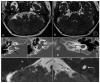

Labyrinthine aplasia, microtia, and microdontia (LAMM) is an autosomal recessive condition causing profound congenital deafness, complete absence of inner ear structures (usually Michel's aplasia), microtia (usually type 1) and microdontia. To date, several families have been described with this condition and a number of mutations has been reported. We report on eight further cases of LAMM syndrome including three novel mutations, c. 173T>C p.L58P; c. 284G>A p.(Arg95Gln) and c.325_327delinsA p.(Glu109Thrfs*18). Congenital deafness was the primary presenting feature in all affected individuals and consanguinity in all but two families. We compare the features in our patients to those previously reported in LAMM, and describe a milder, asymmetrical phenotype associated with FGF3 mutations.